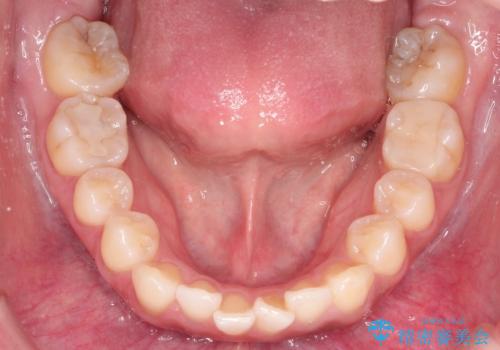

- 患者様は、奥歯(臼歯部)の反対咬合を主訴に来院されました。反対咬合は、噛み合わせのズレや顎の成長に影響を与える可能性があるため、早期の治療が重要です。診断の結果、上顎の幅が不足していることが原因と判明し、MARPE(骨固定式上顎急速拡大装置)を用いて上顎を広げる治療を計画しました。その後、歯列の調整のために審美ワイヤー矯正を行う方針としました。

MARPEを使用して上顎を拡大し、適切な歯列のスペースを確保しました。この拡大によって、反対咬合が改善され、正常な噛み合わせへと誘導できました。その後、目立ちにくいブラケットと白いワイヤーを使用した審美ワイヤー矯正を行い、歯列を整えました。治療が進むにつれ、噛み合わせのバランスが良くなり、見た目も自然な仕上がりに。